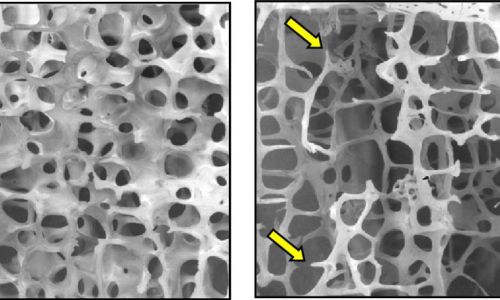

Αποτελούν μεταβολικά σύνδρομα των οστών στα οποία εμφανίζεται σταδιακή μείωση της οστικής μάζας και διαταραχή της οστικής μικροαρχιτεκτονικής ως αποτέλεσμα της γήρανσης του ατόμου (ηλικιακός παράγοντας), της εμφάνισης εμμηνόπαυσης (μετεμμηνοπαυσιακή οστεοπόρωση) καθώς και σε άλλους δευτεροπαθείς παράγοντες.

Η διάγνωση γίνεται με μέτρηση της οστικής πυκνότητας του ασθενούς (Τ score).

Η πάθηση εμφανίζει αυξημένη συχνότητα σε ποσοστό 4:1 στις γυναίκες ενώ συνδέεται με αυξημένο κίνδυνο εμφάνισης οστεοπορωτικών καταγμάτων ισχίου, οσφύος και πηχεοκαρπικής.

Η θεραπεία αφορά κυρίως φαρμακευτική αγωγή, χορήγηση ασβεστίου και βιταμίνης D καθώς και έναρξη καθημερινής άσκησης.